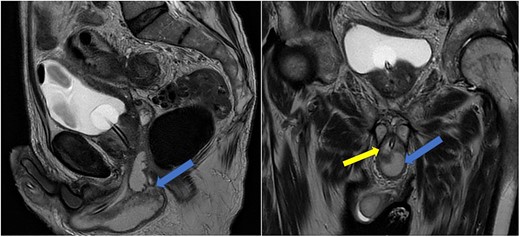

Imaging was suggestive of an infected Cowper’s syringocele. As the patient was clinically stable, a trial of antibiotic therapy was suggested. Repeat MRI a week later showed that the collection had extended into the corpus spongiosum, which now appeared expanded with the fluid density signal (Fig. 1). On a review, the urethral catheter was thought to be impairing potential drainage of the collection. It was removed, and a suprapubic catheter was inserted. Ultrasound guided aspiration failed to drain a significant amount of pus, which also grew S. anginosus. There was also radiological suspicion of a colovesical fistula. The patient was reviewed by the colorectal surgeons, who felt that as there were no other symptoms relating to the fistula, and the patient was physiologically frail, and defunctioning of the bowel would be inappropriate. Likewise, the patient was deemed too frail for any surgical management of the collection. He was discharged after a total of 6 weeks’ antibiotics. Repeat MRI 4 months later (Fig. 2) showed a smaller but persistent collection.

Case 1: sagittal and coronal T2-weighted images showing the collection (blue arrow) inferior to the prostate, and involving the corpus spongiosum (yellow arrow).